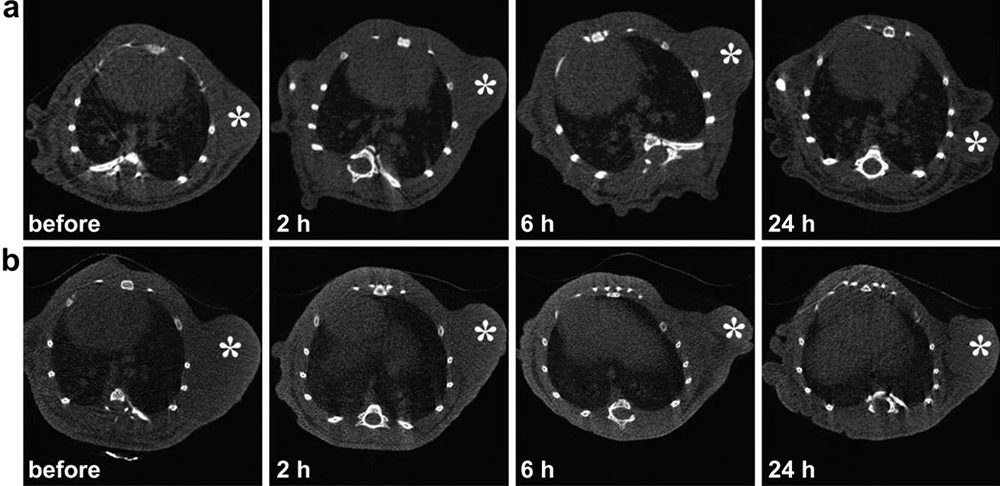

There are numerous natural polymer-based nanocarriers like liposomes, micelles, and micro- and nano-emulsions which could tagged or complex with the CT imaging agent. Organic or inorganic nanoparticles (gold, dendrimer, fullerenes, and silver) mediated CT contrast agents can prolong their blood circulation time. Recent studies suggest that dendrimers have great potential as polymeric X-ray contrast agents due to their distinct characteristic features, such as high X-ray attenuation, excellent water solubility, lesser osmolarity, hydrophilicity, and good chemical stability. Dendrimers are also observed to have prolonged intravascular bioavailability in animal models. Dendrimers are the best nano-scaffold for next-generation iodinated contrast agents by virtue of the suitable numerous surface groups as well as safe use of iodine. PEGylated dendrimers tagged with iohexol exhibited better tumor angiogenesis as compared to pure iohexol in the animal models because of low toxicity and blood pooling. Dendrimers are the key players in the biomedical research due to their synthetic macromolecular globular shape even after those get coupled with the numerous ligands or radiolabeled moieties (25). In order to evaluate the ability of targeted dual mode CT/MR imaging of tumors, the targeted Gd-Au DENPs-FA and the non-targeted Gde Au DENPs ([Au] ¼ 0.1 M, 200 mL) were intravenously injected into two groups of nude mice bearing KB xenograft tumors via tail vein. CT images were captured before (0 h) and after injection (2, 6, and 24 h) using a Micro-CT system as depicted in Figure 6 (26). The radiopaque moiety, tetra-iodobenzene derivative was attached to the dendrimers moiety for the first time to visualize its blood circulation pool time. Other class of dendrimers, like starburst PAMAM dendrimers tethered with the tri-idobenzene derivative (water-soluble) exhibited its prolonged blood half-life (27). Moreover, poly-lysine dendrimers were tagged with iobitridol (trade name Xenetix) contrast agent at each terminal group of its dendritic architecture. The use of high M.W. imaging agent with dendritic structures has exhibited extended blood half-life and increased the peak X-ray attenuation at the time-interval of diagnosis. Their accumulation in liver and spleen were also increased by the reticuloendothelial system.

Figure 6Representative transection CT images of mice bearing transplanted KB tumors after intravenous injection of non-targeted GdeAu DENPs (a) and targeted GdeAu DENPs-FA (b) for 0, 2, 6, and 24 h, respectively. The white star indicates the tumor area. Used with permission from (25).